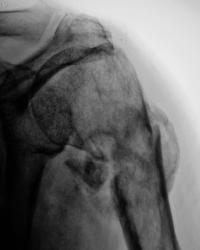

Пациент направлен в рентгеновский кабинет для рентгенографии плечевого сустава. Травма. Произведена рентгенография в прямой проекции.

1.Perelom.1..JPG

После наложения гипсовой повязки, хирургами пациент на контроль направлен не был.

После снятия гипсовой повязки, пациент направлен на "рентген-контроль" для анализа процесса консолидации.